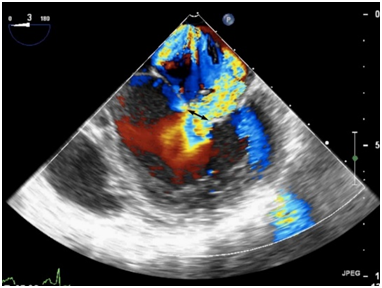

反流束的方向也很重要,其不仅仅是病因学的线索,也是严重程度的一个征象。中心性反流可由瓣环扩张或心室功能不全引起,偏心性反流(图19)常常由二尖瓣结构本身异常引起的,可认为出现偏心性的贴壁反流束属于中度以上反流[23]

图19偏心性二尖瓣反流食管中段四腔心切面二尖瓣彩色多普勒血流成像,可见重度MR沿左房内侧壁走行达心房顶部。